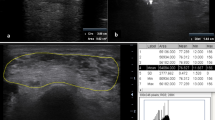

Figure 1 shows the muscles of the lower limbs which have been assessed. The tibialis posterior (TP) was not evaluated according to the poor quality of visualization at calf MRI.

Thigh and calf single muscle ROIs and compartments. Thigh (A) and calf (B) single muscle ROI of a healthy control superimposed on multi-echo spin-echo (ME-SE) sequence (1st echo) to extract water T2 values and on multi-echo gradient-echo (ME-GRE) sequence (1st echo) to obtain fat fraction maps. Thigh and calf compartments are reported on the right